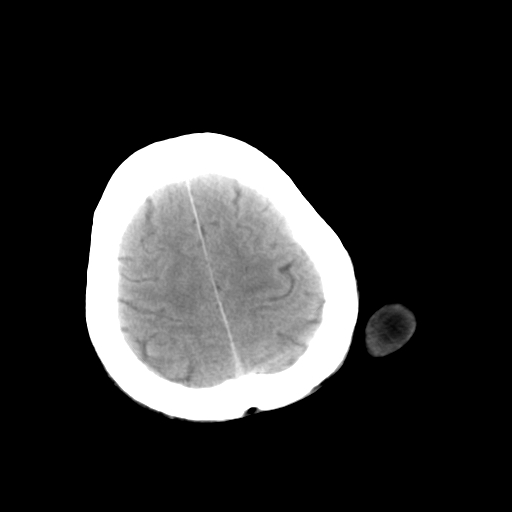

标题: CT25147:男,62岁,右侧肢体活动障碍不灵活三天。 [打印本页]

男,62岁,右侧肢体活动障碍不灵活三天,左侧头皮肿物十余年(ct值8hu)。

1)多发性腔隙性脑梗塞。2)脑白质病。3)脑萎缩。4)左侧枕顶部头皮下皮样囊肿,不排除脂肪瘤。

1)多发性腔隙性脑梗塞。2)脑白质病。3)脑萎缩。4)左侧枕顶部头皮下皮样囊肿或表皮样囊肿。